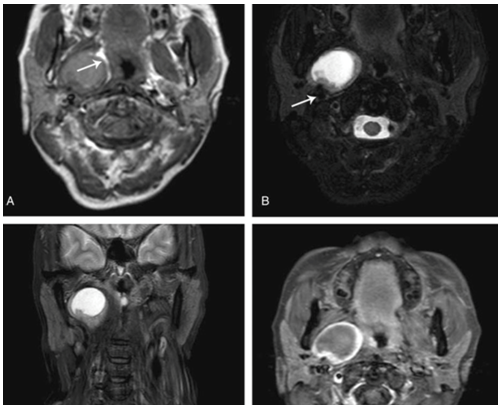

一位52岁的中国女性于2017年1月被送到耳鼻喉科门诊,主诉是喝草药酒后喉咙痛。体格检查显示右侧咽外侧壁肿胀,咽喉红肿,无异常分泌物或溃疡。口外检查肿胀、压痛或淋巴结肿大均隐形。增强型计算机断层扫描(CT)和磁共振成像(MRI)扫描显示右侧PPS主要为囊性肿块,直径为33mm。这种定位良好的肿块在静脉注射钆后表现为周边增强(图1)。

图1